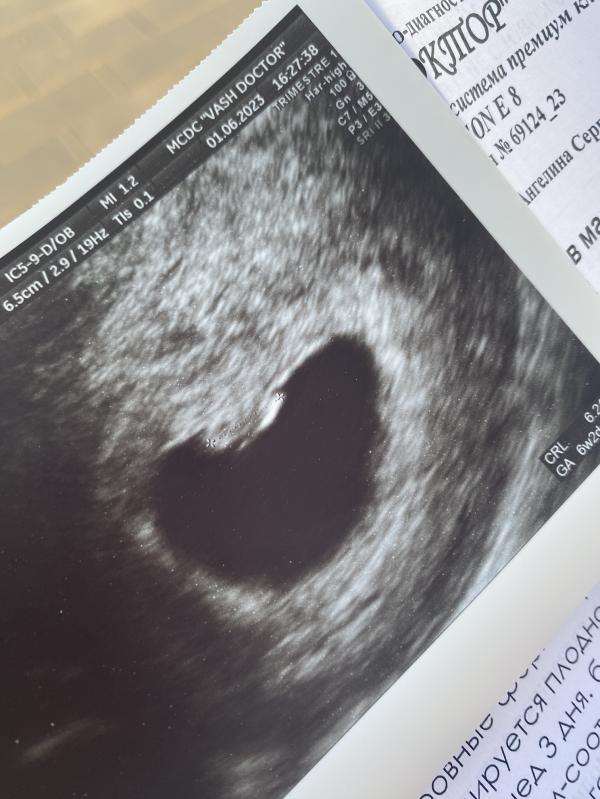

Растём🥹❤️

02.06.2023